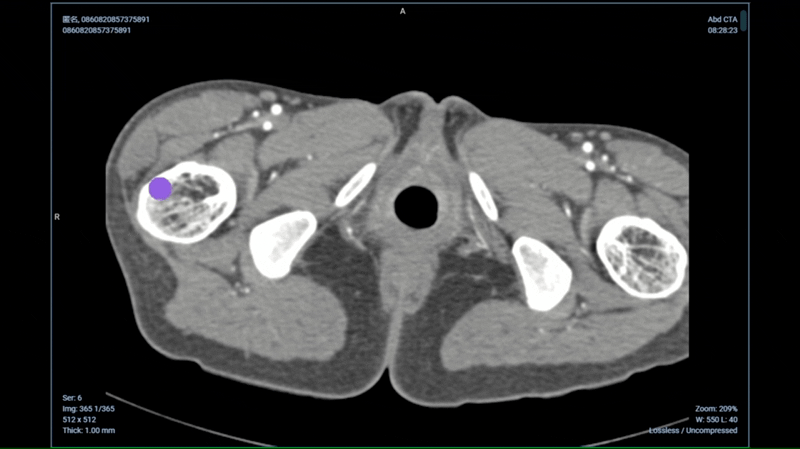

多人、多团队、多中心医学影像云原生协同标注与高级可视化平台。通过医学影像分割大模型及多种AI技术,灵活支撑不同规模的数据标注团队高效完成医学影像协同标注工作,支持自动标注、半自动标注、手工标注、三维标注、形态学测量,提高放射学影像的标注效率和质量。

业内领先的医学影像标注平台,以基于Web云原生的模式,通过医学影像分割大模型及多种AI技术,灵活支撑不同规模的数据标注团队高效完成医学影像标注工作。提供基于医学影像分割大模型MISM、以及深度学习、机器学习自动化标注工具,自动分割医学影像中的器官、病灶与组织,为医学研究提供金标准数据,提高手术规划的效率。